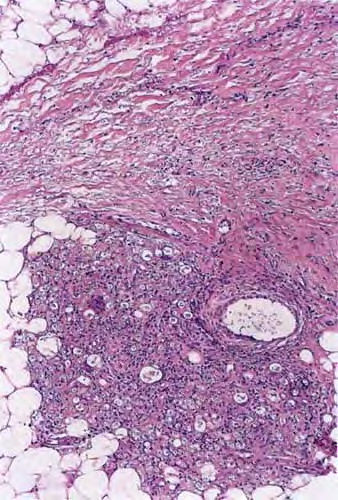

Histopathologically, the signature cell of ENL is the neutrophil, which may be abundant, scant, or absent, if an old lesion is sampled . Other common features include an increase in lymphocytes, a thickened epidermis, and a lobular panniculitis. Vasculitis is uncommon. The usual histologic pattern is a “bottom heavy” infiltrate, preferring the deep dermis and subcutis.